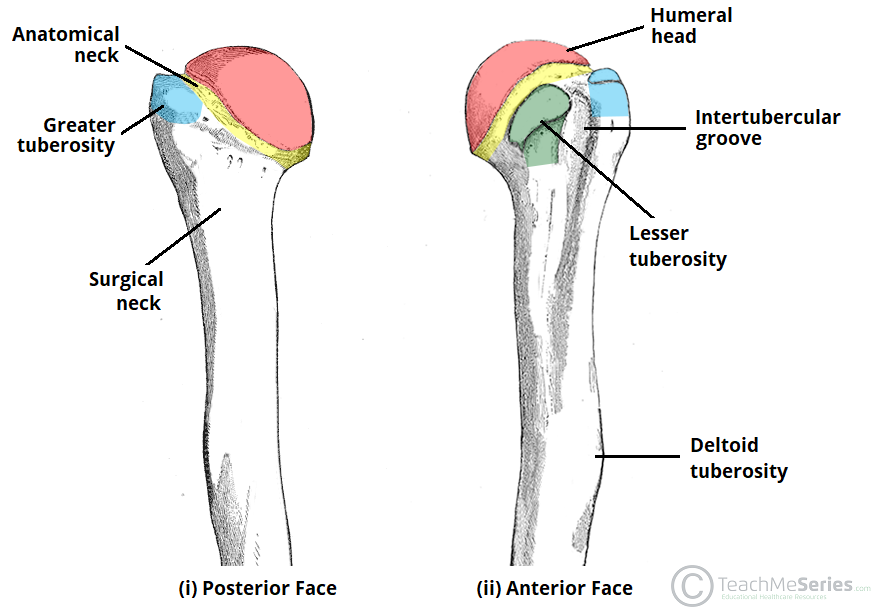

Review this diagram of the portions of the proximal humerus.

Weakest portion of the humerus and the most common place of fracture

Surgical Neck